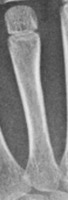

Medical Education: Using the LY-batch1 model to create interactive learning tools for medical students, helping them identify and differentiate various Metacarpus classes and expand their knowledge of anatomical structures.

Orthopedic Diagnostics: Assisting healthcare professionals in analyzing X-ray or MRI images to identify Metacarpus abnormalities or fractures, allowing for quicker and more accurate diagnosis and treatment planning.